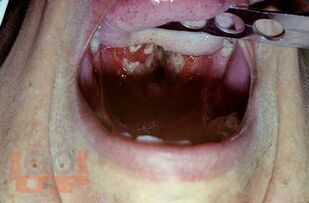

В основу монографии положены результаты собственных наблюдений и исследований авторов, касающиеся более 3500 больных с различными клиническими формами дифтерии. Клиника заболевания представлена в сопоставлении со сходными с нею другими инфекционными болезнями. Большое внимание уделено совершенно новым аспектам патогенеза дифтерии и особенностям ее течения в современных условиях, факторам риска неблагоприятного течения инфекционного процесса, причинам летального исхода болезни, а также разработанной и опробованной авторами на практике методике организации эффективного лечения больных в период нахождения их на догоспитальном и госпиталь ном этапах, включающей оказание неотложной помощи и ведение интенсивной терапии.